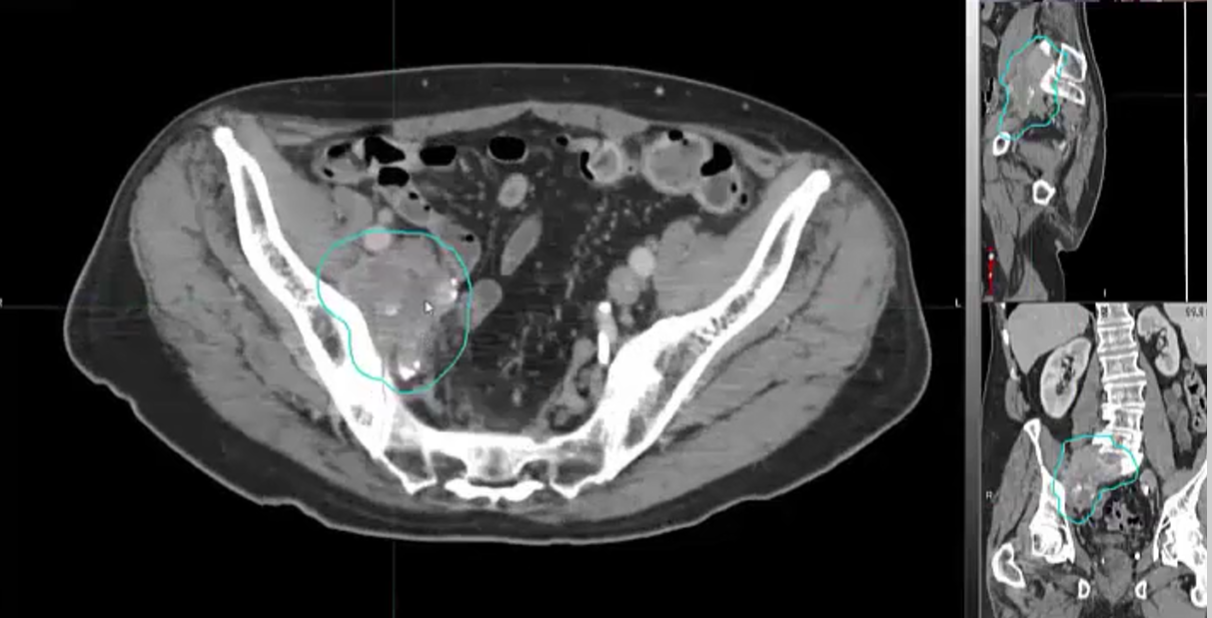

urethral tumor, urothelial carcinoma, PET, CT, palliative treatment, mediastinal nodes, biopsy, prostate gland, PSMA, false positive, pelvis with nodes, bone lesions, PSA, bladder